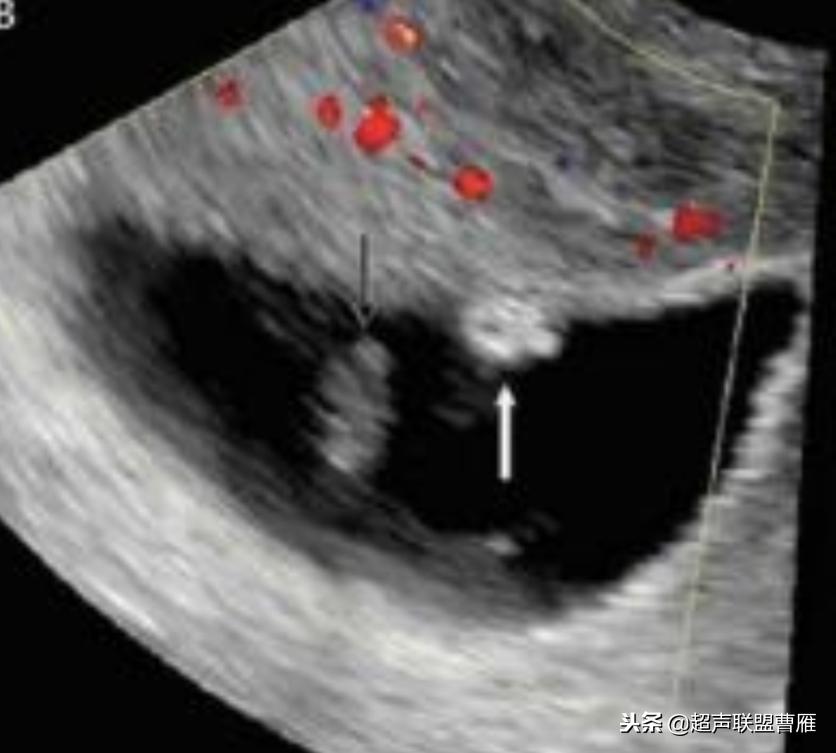

卵黄囊的大小与形态异常与胚胎的发育是否正常关系密切。卵黄囊增大,直径超过6.1cm,胚胎的预后不良。

卵黄囊的大小与形态异常与胚胎的发育是否正常关系密切。,形态异常的卵黄囊预后不良。

孕龄5.8周,胚极2.5mm,卵黄囊8mm,死胎

孕龄7+5周卵黄囊10.3mmx9.5mm,胚胎死亡

有的文献将卵黄囊内径的最大限度定为6.1mm

卵黄囊11*6.9mm 大卵黄囊